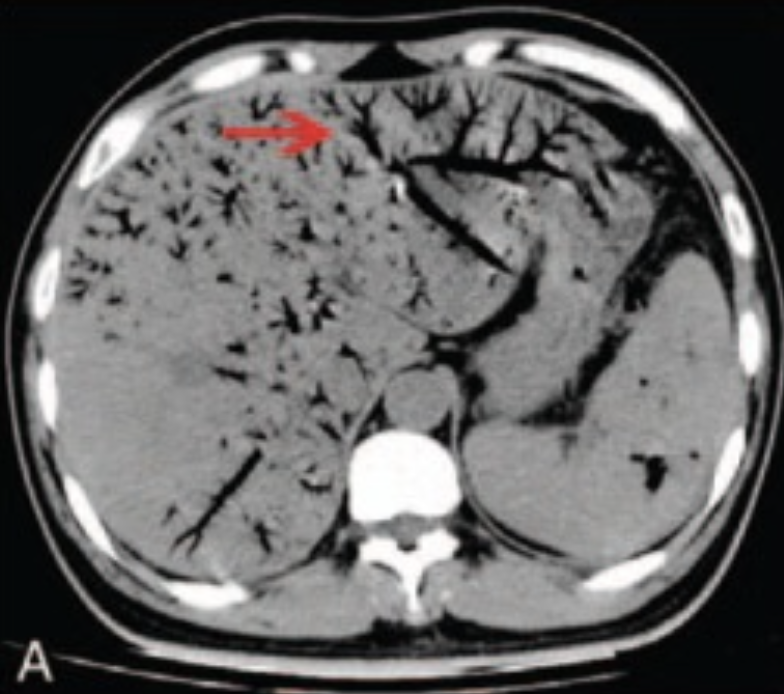

- ガスは主に肝内門脈に見られ門脈気腫などとも言われる

- 胆道気腫と鑑別の方法は分布の仕方である。門脈ガスは門脈血流に従い肝臓の辺縁2cm以内に細かい樹枝状に分布し重力に従い肝左葉→右葉前区域→右葉後区域へ分布する